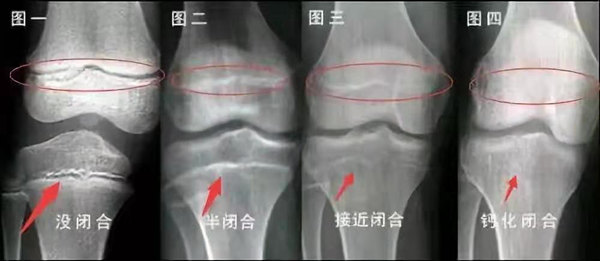

我們都知道,人體的高矮是由骨骼的生長發(fā)育決定的,特別是下肢長骨。長骨呈長管狀,在長骨的兩端有一種專管骨骼生長的骺軟骨,它與干骺端之間有一盤狀軟骨結(jié)構(gòu)稱為骺板(線),在幼兒的X光片上表現(xiàn)為一條較寬的透光帶。 (見下圖)

未成年時(shí)隨著年齡的增加骺軟骨端不斷骨化,骨骼就不斷增長。當(dāng)骨骺線完全閉合時(shí)骨骼就停止生長,個(gè)子也就不再增長了。一般骨骺端完全閉合的年齡是18~20歲左右。

骨骺線提前閉合最多見的情況是性早熟,而這也是很多醫(yī)生專家建議孩子進(jìn)行骨齡測量的原因之一。另外,在兒童時(shí)期大量補(bǔ)鈣也會(huì)使骨骺端提前過早閉合。

一般來說,女孩的骨齡超過14歲,男孩的骨齡超過16歲,這時(shí)其骨骺線已接近閉合,基本沒有長高的機(jī)會(huì)了。

因此,越早了解骨骺線閉合情況,越早干預(yù),孩子長高的可能性越大。